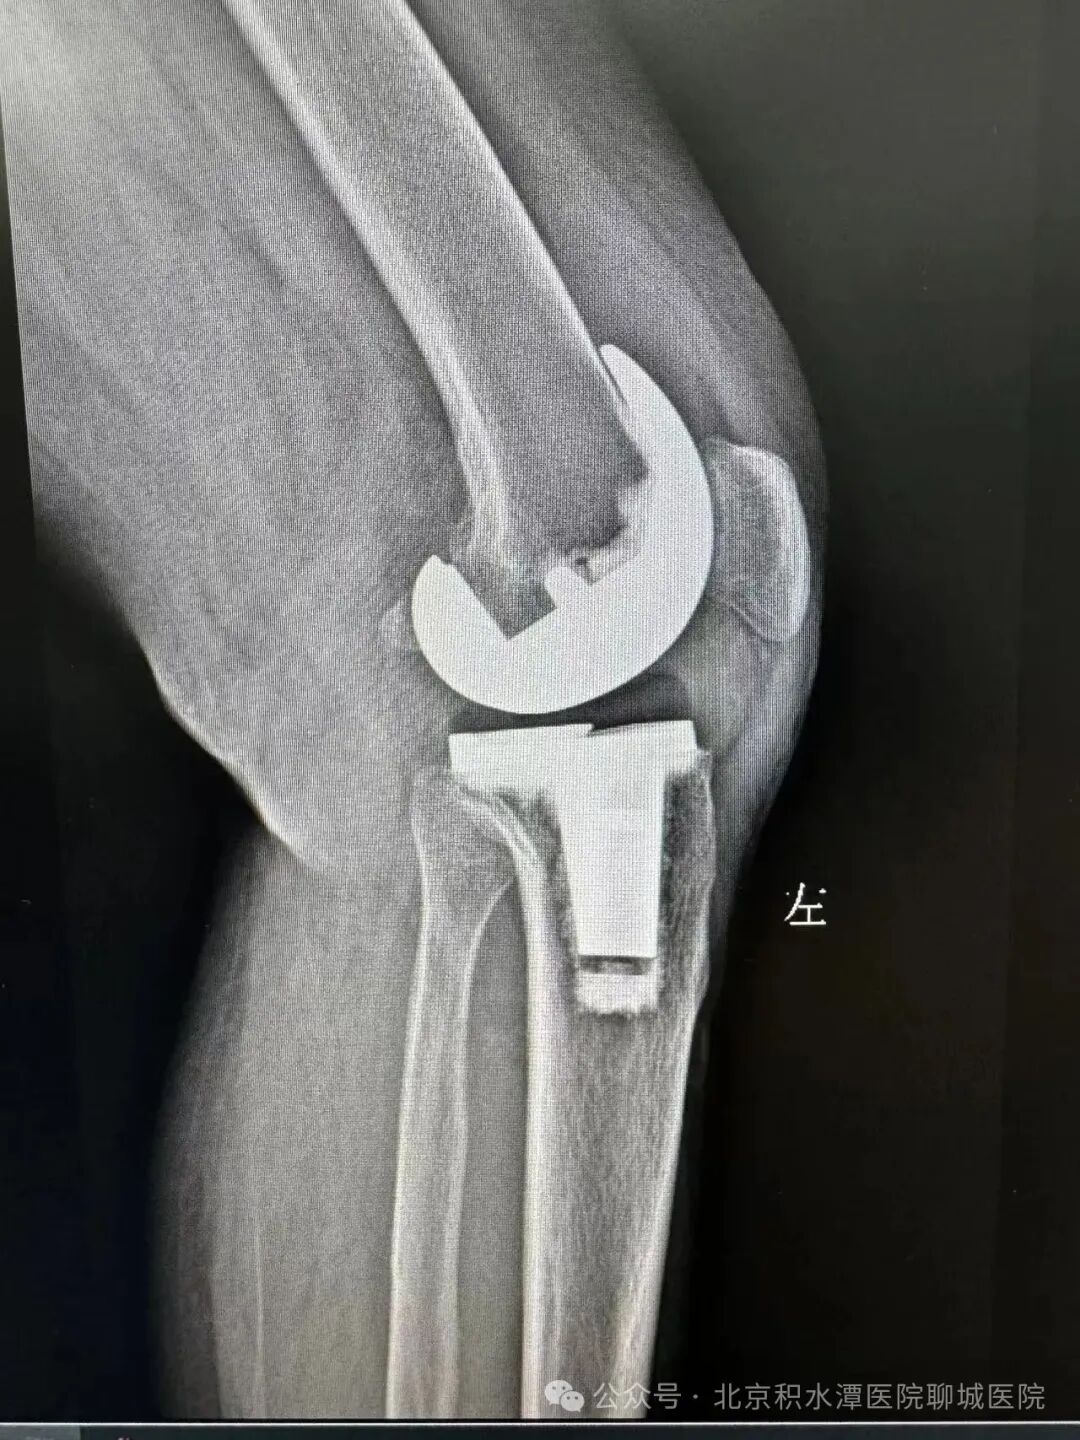

(术后影像)

基于对“隐匿性关节不稳”的清晰认知,徐辉教授团队制定了科学且极具突破性的手术方案,在保留患者自身骨量的同时,精准移除失效部件,并创新性地采用非水泥生物型假体固定技术(聊城首例)。该技术依靠假体表面特殊的生物活性涂层,诱导患者自身骨组织在术后长入假体微孔,实现更持久、更稳固的生物学骨整合,相较于传统骨水泥固定,尤其适用于翻修病例中骨条件相对较好的患者,大大提升了假体的长期稳定性。同时,手术选用了先进的“旋转平台型聚乙烯衬垫”,这一设计允许衬垫在金属底座上发生生理性旋转,显著降低了假体间的剪切应力和聚乙烯磨损,进一步提高了关节的包容性和稳定性,有效降低了远期再松动的风险。